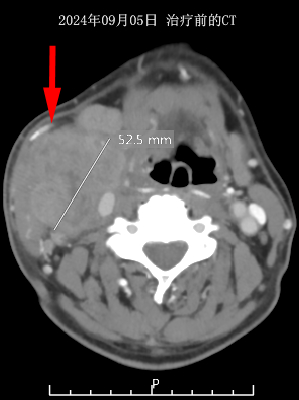

2024年9月5日,67岁的许先生因右颈部肿物持续增大2个月到济南市五院就诊。巨大的肿块严重影响了他的吞咽功能和颈部活动,这让他内心蒙上了一层沉重的阴影。经过全面细致的检查以及颈部肿物穿刺活检,许先生被确诊为局部晚期下咽癌(IVb期)。由于肿瘤侵犯范围广泛,他已失去了手术机会。

治疗前后对比

经过一段时间的系统治疗,奇迹出现了。患者右颈部巨瘤已基本消失不见,颈部形态与活动功能大幅改善。复查CT影像清晰显示,肿瘤病灶达到完全缓解(CR)标准。从吞咽困难到正常进食,从活动受限到行动自如,这份康复不仅让许先生重获健康体魄,更让他重新燃起了对生活的希望。

治疗前后CT对比